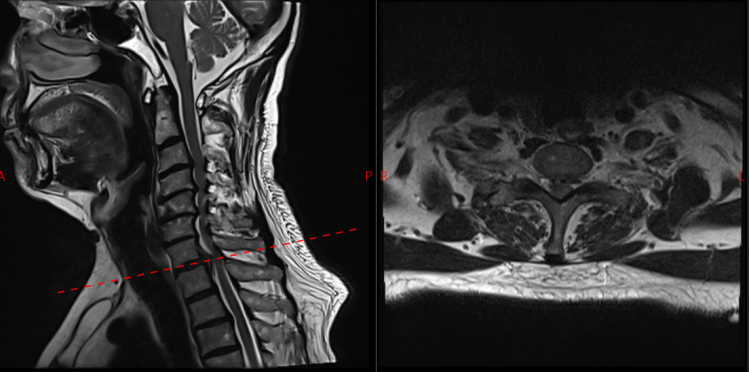

面对这一特殊情况,吴静晔主任没有急于下结论,而是为患者进行了细致全面的检查,最终精准诊断为脊髓型颈椎病。而进一步检查显示,患者存在C3-T1多节段狭窄,病情复杂且手术节段较多,这无疑给治疗带来了巨大挑战。

常规的治疗方案是颈后路C3-T1开门手术。虽能实现彻底减压,但手术损伤较大,对于78岁高龄的患者来说,是极大的考验。

为最大程度降低手术损伤,保障手术安全,吴静晔主任、王肖虎主任带领团队反复研讨,最终制定了更贴合患者情况的手术方案——C7-T2节段全椎板切除减压、髓核摘除、椎弓根螺钉内固定术。

看似确定了治疗方向,真正的难题才刚刚开始。该手术区域解剖结构极其复杂,毗邻人体重要的神经、血管,堪称脊柱外科的“珠峰”。

尤其是C7-T2椎弓根螺钉置入环节,传统手术极度依赖术中C臂透视,却因肩部遮挡,透视、定位极为困难,不仅手术视野受限、置钉难度陡增,螺钉还极易误入椎管,导致术中减压不充分,手术效果完全依赖主刀医生的丰富经验和精湛技术,是业内公认的“硬骨头”手术。